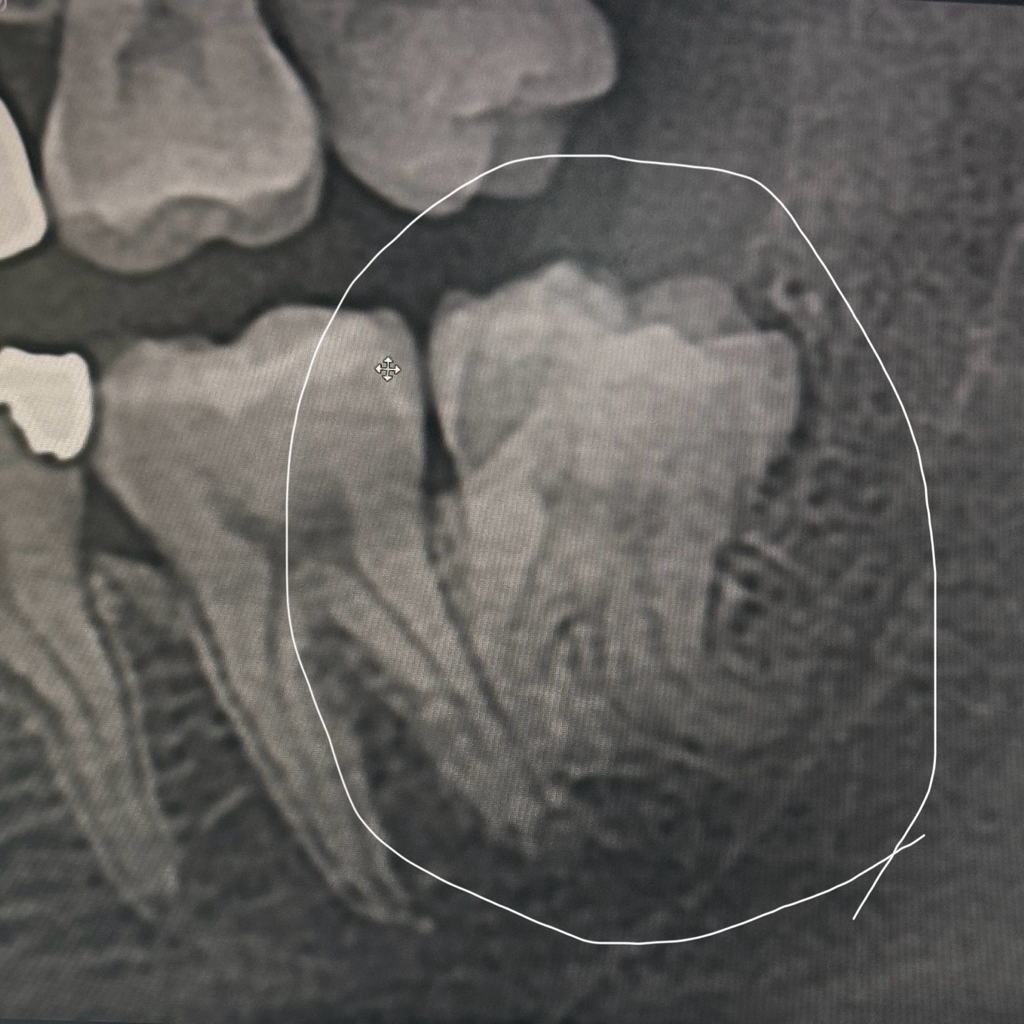

사진은 제 사랑니에요 ㅠ

• 1번 째 사진

사진에 있는 왼쪽 아래 사랑니는 뿌리가 반대로 굉장히 휘어져 있기 때문에 사랑니 발치 시 뿌리가 부서질 확률이 매우 높습니다.

그래서 발치 중에 너무 무리해서 뽑으려고 하지 않고 뿌리 끝을 남겨둘 수도 있습니다. 또한 신경과 근접해 있기도 하기 때문에 발치의 난이도는 높긴 합니다.

발치 중 신경손상의 가능성도 있긴 합니다. 이런 경우 일시적으로 아래턱 마비의 증상이 있을 수 있습니다. 이런 마비의 증상은 일시적일 수도 있고 아니면 최대 6개월~1년 지속될 가능성도 있긴 합니다.